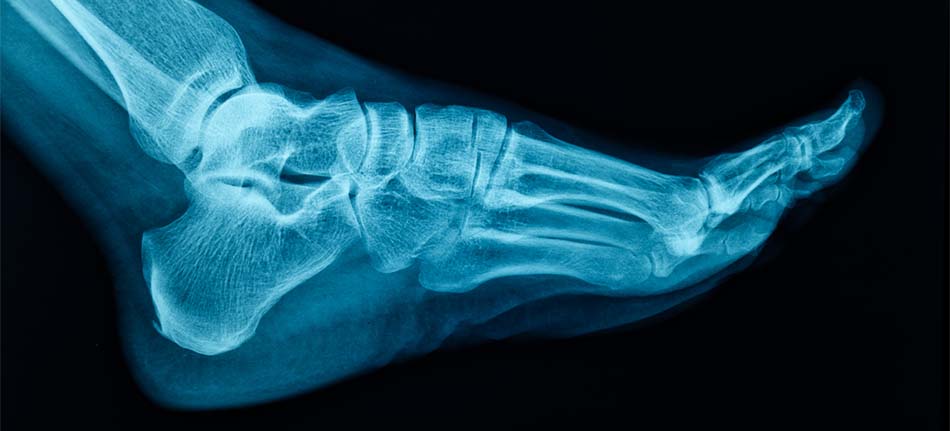

Digital X-Rays in Sarasota, FL

At Sarasota Foot Care Center, we use the latest digital X-ray technology to enhance the accuracy of our diagnoses and treatment plans. Digital X-rays offer numerous advantages over traditional film-based X-rays, making them a powerful tool in helping us provide the best care for your foot and ankle health.

Digital X-rays allow us to quickly and accurately assess the condition of your feet and ankles. They provide high-quality images with minimal radiation exposure, allowing for better-informed decision-making and faster, more efficient treatment.

• High-Resolution Images: Digital X-ray technology produces high-quality, detailed images that help us detect fractures, bone abnormalities, arthritis, joint issues, and other foot or ankle conditions with greater clarity.